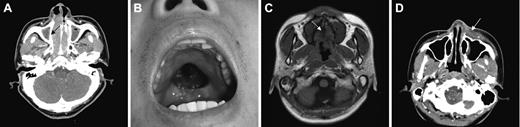

Local tumor invasiveness. (A) Thinning of right medial wall of maxillary bone (arrow) in CT of paranasal sinuses. (B) Palatal perforation on physical examination. (C) High signal intensity of hard palate is not delineated in T1-weighted MRI (arrow). (D) Skin infiltration by tumor (arrow) in CT of paranasal sinuses. Picture was taken with an Olympus Camedia C4000Z camera (Olympus, Tokyo, Japan). Adobe Photoshop 6.0 was used to process images (Adobe, San Jose, CA).

LTI was defined as bony invasion or perforation or invasion of the skin. The involved bony structures included the anterior and medial walls of maxillary sinuses; the medial walls of the orbit; the anterior and inferior walls of ethmoidal sinuses; the skull base; and the inferior walls of frontal sinuses, hard palate, nasal bone, and nasal septal bones (perpendicular plate of ethmoid and vomer). We defined the extent of bone involvements based on CT and physical findings. Thinning or disorganized structure of bones due to the tumor was regarded as bony invasion (Figure 1A), and bone defect caused by the tumor was regarded as bony perforation (Figure 1B). Disruption of high signal intensity of bone marrow on T1-weighted MRI was also considered as bony invasion (Figure 1C). The infiltration of overlying skin around the tumor was regarded as skin invasion (Figure 1D). The CT/MRI findings of the head and neck were reviewed by radiologists (J.-H.K. and K.-H.C.) blinded to clinical outcomes.